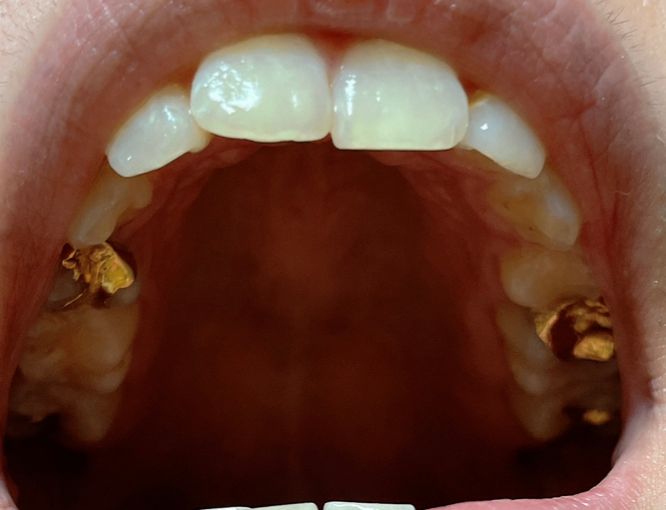

사진4. 윗니 아치 (사진이 살짝 좌측에서 찍혔으나 아치는 살아있습니다. 이전 교정 시 윗니 양쪽에 각 1개씩 발치했습니다).

• 4번 째 사진